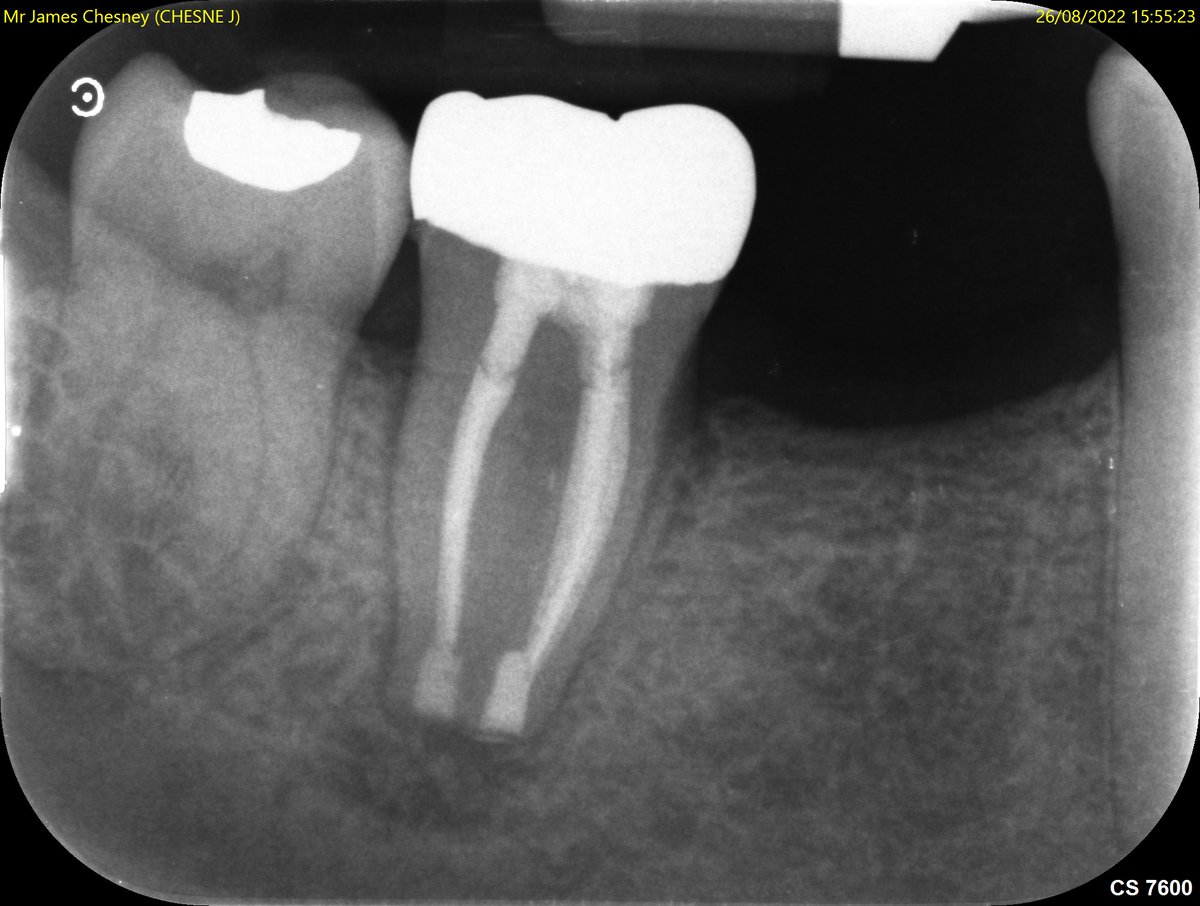

Here in Endoland its Deep Margin Management week! 🤣 in this case simple RCT UR6, core build up using Palodent sectional matrix and PTFE tape Dentsply Sirona UK @BetterEndo #savingteeth #endodontics

Here in Endoland its Deep Margin Management week! 🤣 in this case simple RCT UR6, core build up using Palodent sectional matrix and PTFE tape <a href="/DENTSPLY_UK/">Dentsply Sirona UK</a> @BetterEndo #savingteeth #endodontics